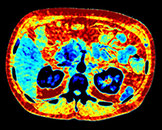

Obraz efektywnej liczby atomowej

Tworzy w oparciu o liczbę atomową tkanki widocznej na obrazie kodowaną kolorem mapę, której można użyć do scharakteryzowania różnych tkanek, np. kamicy nerkowej.